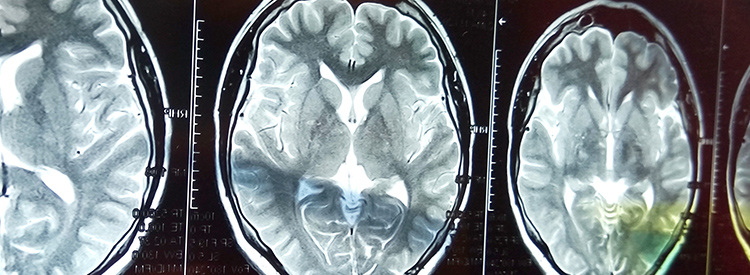

當大腦部分血流被切斷時(shí),就會(huì )發(fā)生中風(fēng)。當這種情況發(fā)生時(shí),失去血液供應的腦組織就會(huì )受傷或死亡。根據大腦受損區域控制的功能,這會(huì )導致身體功能喪失。例如,如果控制左臂運動(dòng)的區域受損,該臂就會(huì )變得虛弱或癱瘓。如果左臂控制感覺(jué)的區域也受到影響,手臂會(huì )麻木,或者也可能有燒灼感或疼痛感。由于大腦控制著(zhù)我們所有的運動(dòng)和感覺(jué),包括視覺(jué)和言語(yǔ),因此幾乎任何事物都可能受到中風(fēng)的影響。

中風(fēng)治療進(jìn)展緩慢。如果在最初幾分鐘內進(jìn)行治療,可以在急診室或醫院使用特殊藥物(阿替普酶或組織纖溶酶原激活劑)來(lái)逆轉或限制缺血性中風(fēng)造成的損害。這種藥物可以分解阻塞血管的凝塊。如果在最初的幾分鐘到幾小時(shí)內使用,可以避免或限制對大腦的任何損害。在使用阿替普酶之前,必須進(jìn)行 CT 成像來(lái)確定中風(fēng)類(lèi)型,以確認中風(fēng)不是出血性的。由于阿替普酶會(huì )分解血栓,因此如果用于出血性中風(fēng),可能會(huì )導致嚴重惡化或死亡。有時(shí)會(huì )治療出血性中風(fēng)以避免進(jìn)一步出血。